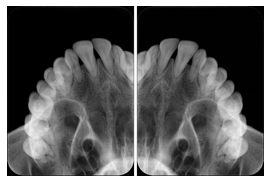

2. A patient requests cosmetic surgery to enhance their facial appearance. The case requires consultation between an orthodontist in New York and an oral surgeon in California. The cephalometric series of 2D projections constructed from a volumetric CT data set that is used for the discussion is arranged by a Structured Display for transfer between the two practitioners.

Cephalometric Series Structured Display

Figure OO-2. Cephalometric Series Structured Display